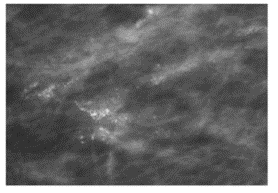

fine pleomorphic

= scary

BR 4 or 5